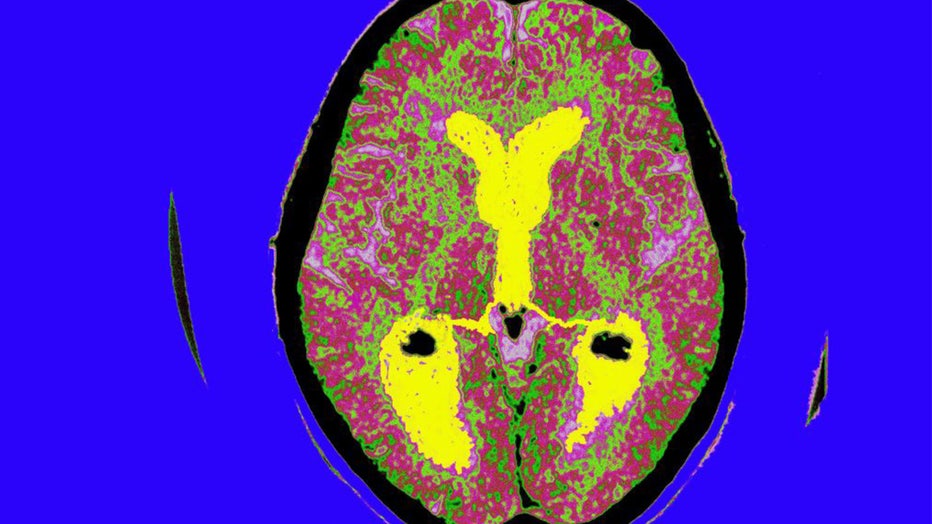

FILE - Toronto Star reporter Joe Hall's brain scan images taken during his visit to the Toronto Western Hospital's MRI room on July 29, 2015. (Brian B. Bettencourt/Toronto Star via Getty Images)

FILE - Toronto Star reporter Joe Hall's brain scan images taken during his visit to the Toronto Western Hospital's MRI room on July 29, 2015 (Brian B. Bettencourt/Toronto Star via Getty Images)

FILE - Alzheimer's Disease, Scan, Brain Of A Patient Affected By Alzheimer's Disease, Axial Section, Median Portion Of Dilated Third Ventricle, Symmetrical Dilation Of Intersections, Whereas The Cortical Horns Are Normal In Size. (BSIP/Universal Images Group via Getty Images)